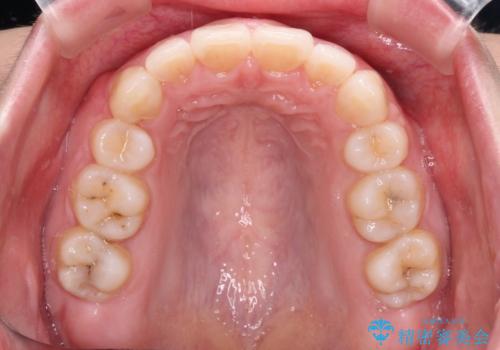

元々上下正中の位置はずれていましたが、治療中によりズレが大きくなったので、元の位置に戻すため治療期間を余計に要しました。

横顔の印象が大きく改善され、患者様には大変満足していただきました。